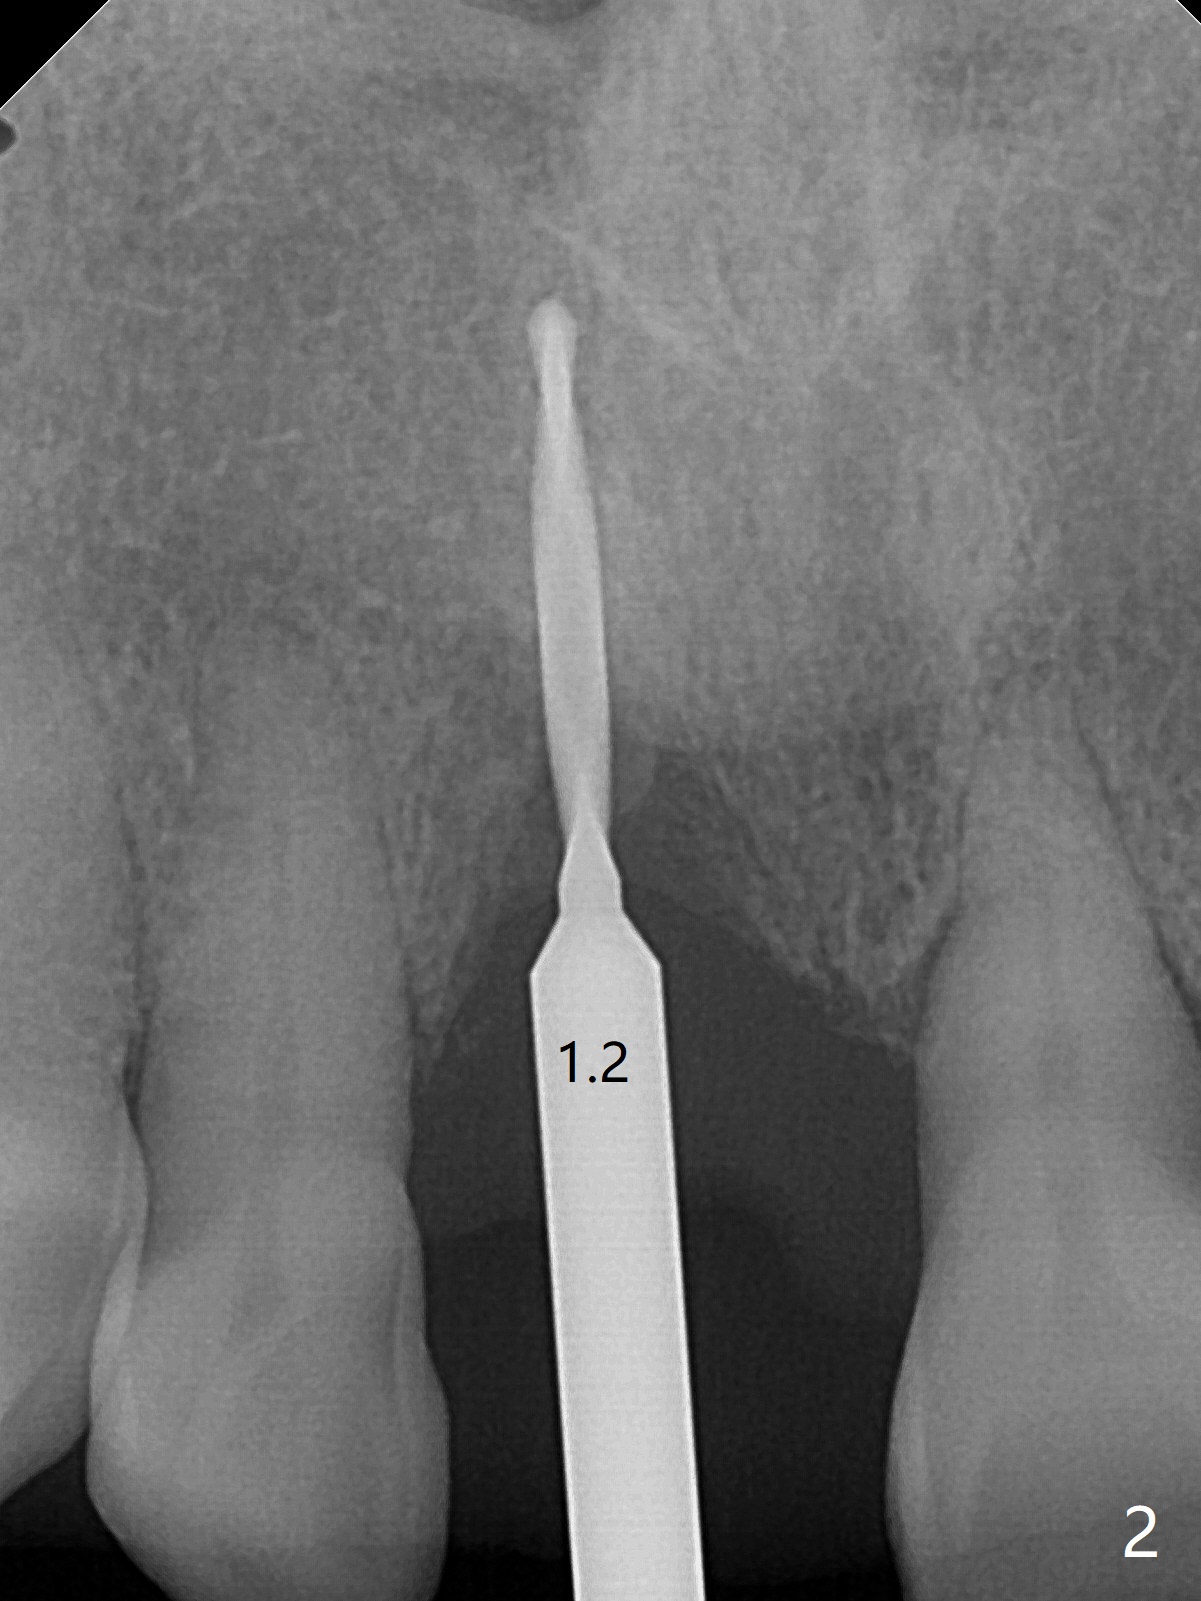

59岁女术前右下1,2切缘磨短后,右上1颊侧移位得到纠正(图一(咬合创伤))。拔牙后证实颊侧骨板缺失,钻洞始于腭侧(图二),当1.5毫米钻头感觉刚穿破鼻底时,置入2.5x14(4)毫米一段式植体,好像进入鼻腔,但是扭力<10Ncm(图三)。把一张PRF膜放入牙槽窝,一端紧贴颊侧牙龈腭侧,另一端放置颊侧牙龈颊侧(图四),然后开始用粘性骨粉(图五,七:*(100%皮质骨))充填颊侧间隙。后者填满时(图五:*),将外面一端PRF翻转覆盖牙槽窝开口,并插入基台固定(图六),最后插入龈下,用临时牙冠固定(图八(T),九(*:PRF))。术后九天牙龈退缩(图十:^),临时牙冠突出(*),后者龈缘和切缘进行调整,缩短(图十一,十二),少许骨粉暴露(图十二:>),十四天后牙龈往下生长,好像形成角化龈(图十三:*)。